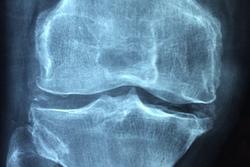

L’articolo di Margaretten e collaboratori, pubblicato sull’International Journal of Clinical Rheumathology, studia le evidenze e le ragioni della comorbilità fra depressione e artrite reumatoide. La depressione si accompagna all’artrite reumatoide nel 13-42% dei casi, a seconda degli studi. Il principale comune denominatore fra le due patologie sembra essere l’infiammazione. L’artrite reumatoide è infatti una patologia di natura infiammatoria, e la sua gravità è funzione dei livelli di citochine presenti nell’organismo. Ma crescenti evidenze indicano come anche la depressione sia una patologia sistemica, caratterizzata da elevati indici infiammatori che vanno ad aggravare l’azione negativa esercitata, sul tono dell’umore, dal dolore e dalla disabilità connessa all’artrite. L’articolo esamina anche i fattori socio-economici predittivi di depressione nelle pazienti con artrite reumatoide: oltre al genere femminile, i più significativi sono la giovane età, l’etnia, l’insufficiente capacità di fronteggiare la malattia (coping strategies) e lo scarso supporto sociale.